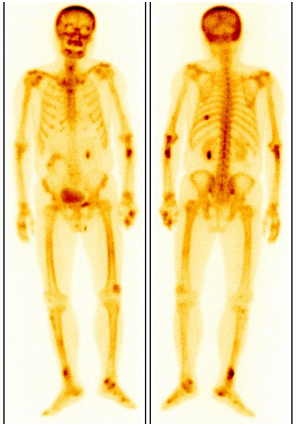

老年男性,因骨痛外院檢查發現骨質破壞,考慮“骨轉移”來診。ECT顯示四肢多發局灶性代謝增高灶并有“黑顱征”,診斷為甲狀旁腺功能亢進性骨病。